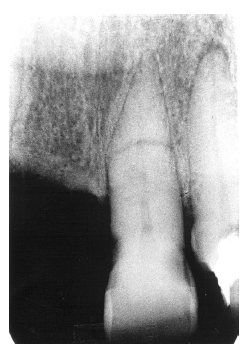

Figure 13 - Apical Periodontal Pathosis

Figure 13

Periapical Granuloma

The periapical granuloma represents the body’s defense mechanism attempting to wall off irritants draining from a non-vital dental pulp. While they cannot be radiologically differentiated from abscesses or cysts, they can be differentiated from normal anatomical landmarks such as the incisive fossa because the periodontal ligament space is widened and the lamina dura is not continuously intact.

Figure 13 illustrates apical periodontal pathosis in the area of the right central incisor. Note the loss of continuity of the lamina dura and the widened periodontal ligament space on the affected side.